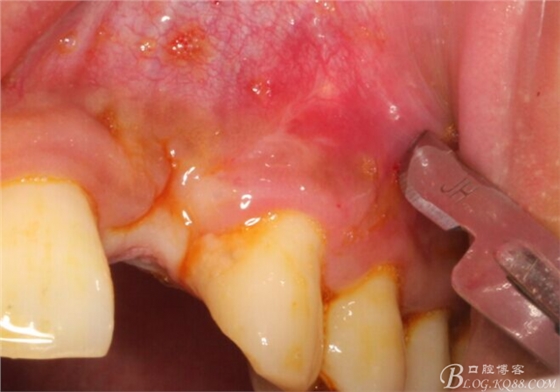

10天拆線一切正常,又過了兩周患者復(fù)診,自述期間無異常??趦?nèi)檢查,真的嚇了一跳,唇側(cè)鼓了個(gè)包,擠壓有白色分泌物溢出,絕對不是膿液,液體排除后,術(shù)區(qū)觸診空虛,外觀塌陷。這時(shí)候考研大夫的時(shí)刻到了,是先觀察一段時(shí)間再說?還是馬上進(jìn)行處理?我的回答是:馬上處理!如果你沒有及時(shí)處理,而是放患者回家觀察,那么接下來會(huì)發(fā)生如下情況:1.回家后患者家屬及親友會(huì)有很多你可以想象得到的討論;2.患者及家屬會(huì)對你產(chǎn)生不信任,勢必會(huì)到其他門診或醫(yī)院檢查,他院大夫會(huì)不會(huì)發(fā)表對你不利的言論;3甚至?xí)蚁嚓P(guān)法律界人士找你討要說法。

于是我果斷告知患者,手術(shù)失敗了,不能拖延,如不及時(shí)處理,炎癥繼續(xù)發(fā)展會(huì)很快波及鄰牙牙槽骨。患者接受我的建議。切開翻瓣,骨粉及生物膜消失了,骨吸收嚴(yán)重,幸運(yùn)的是,因?yàn)樘幚砑皶r(shí),鄰牙骨支持依然存在。